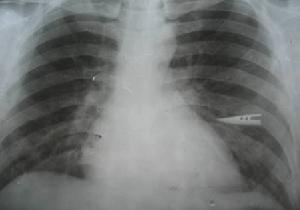

2.胸部X線照片心臟可正常或輕度增大,常伴有肺充血的現象。